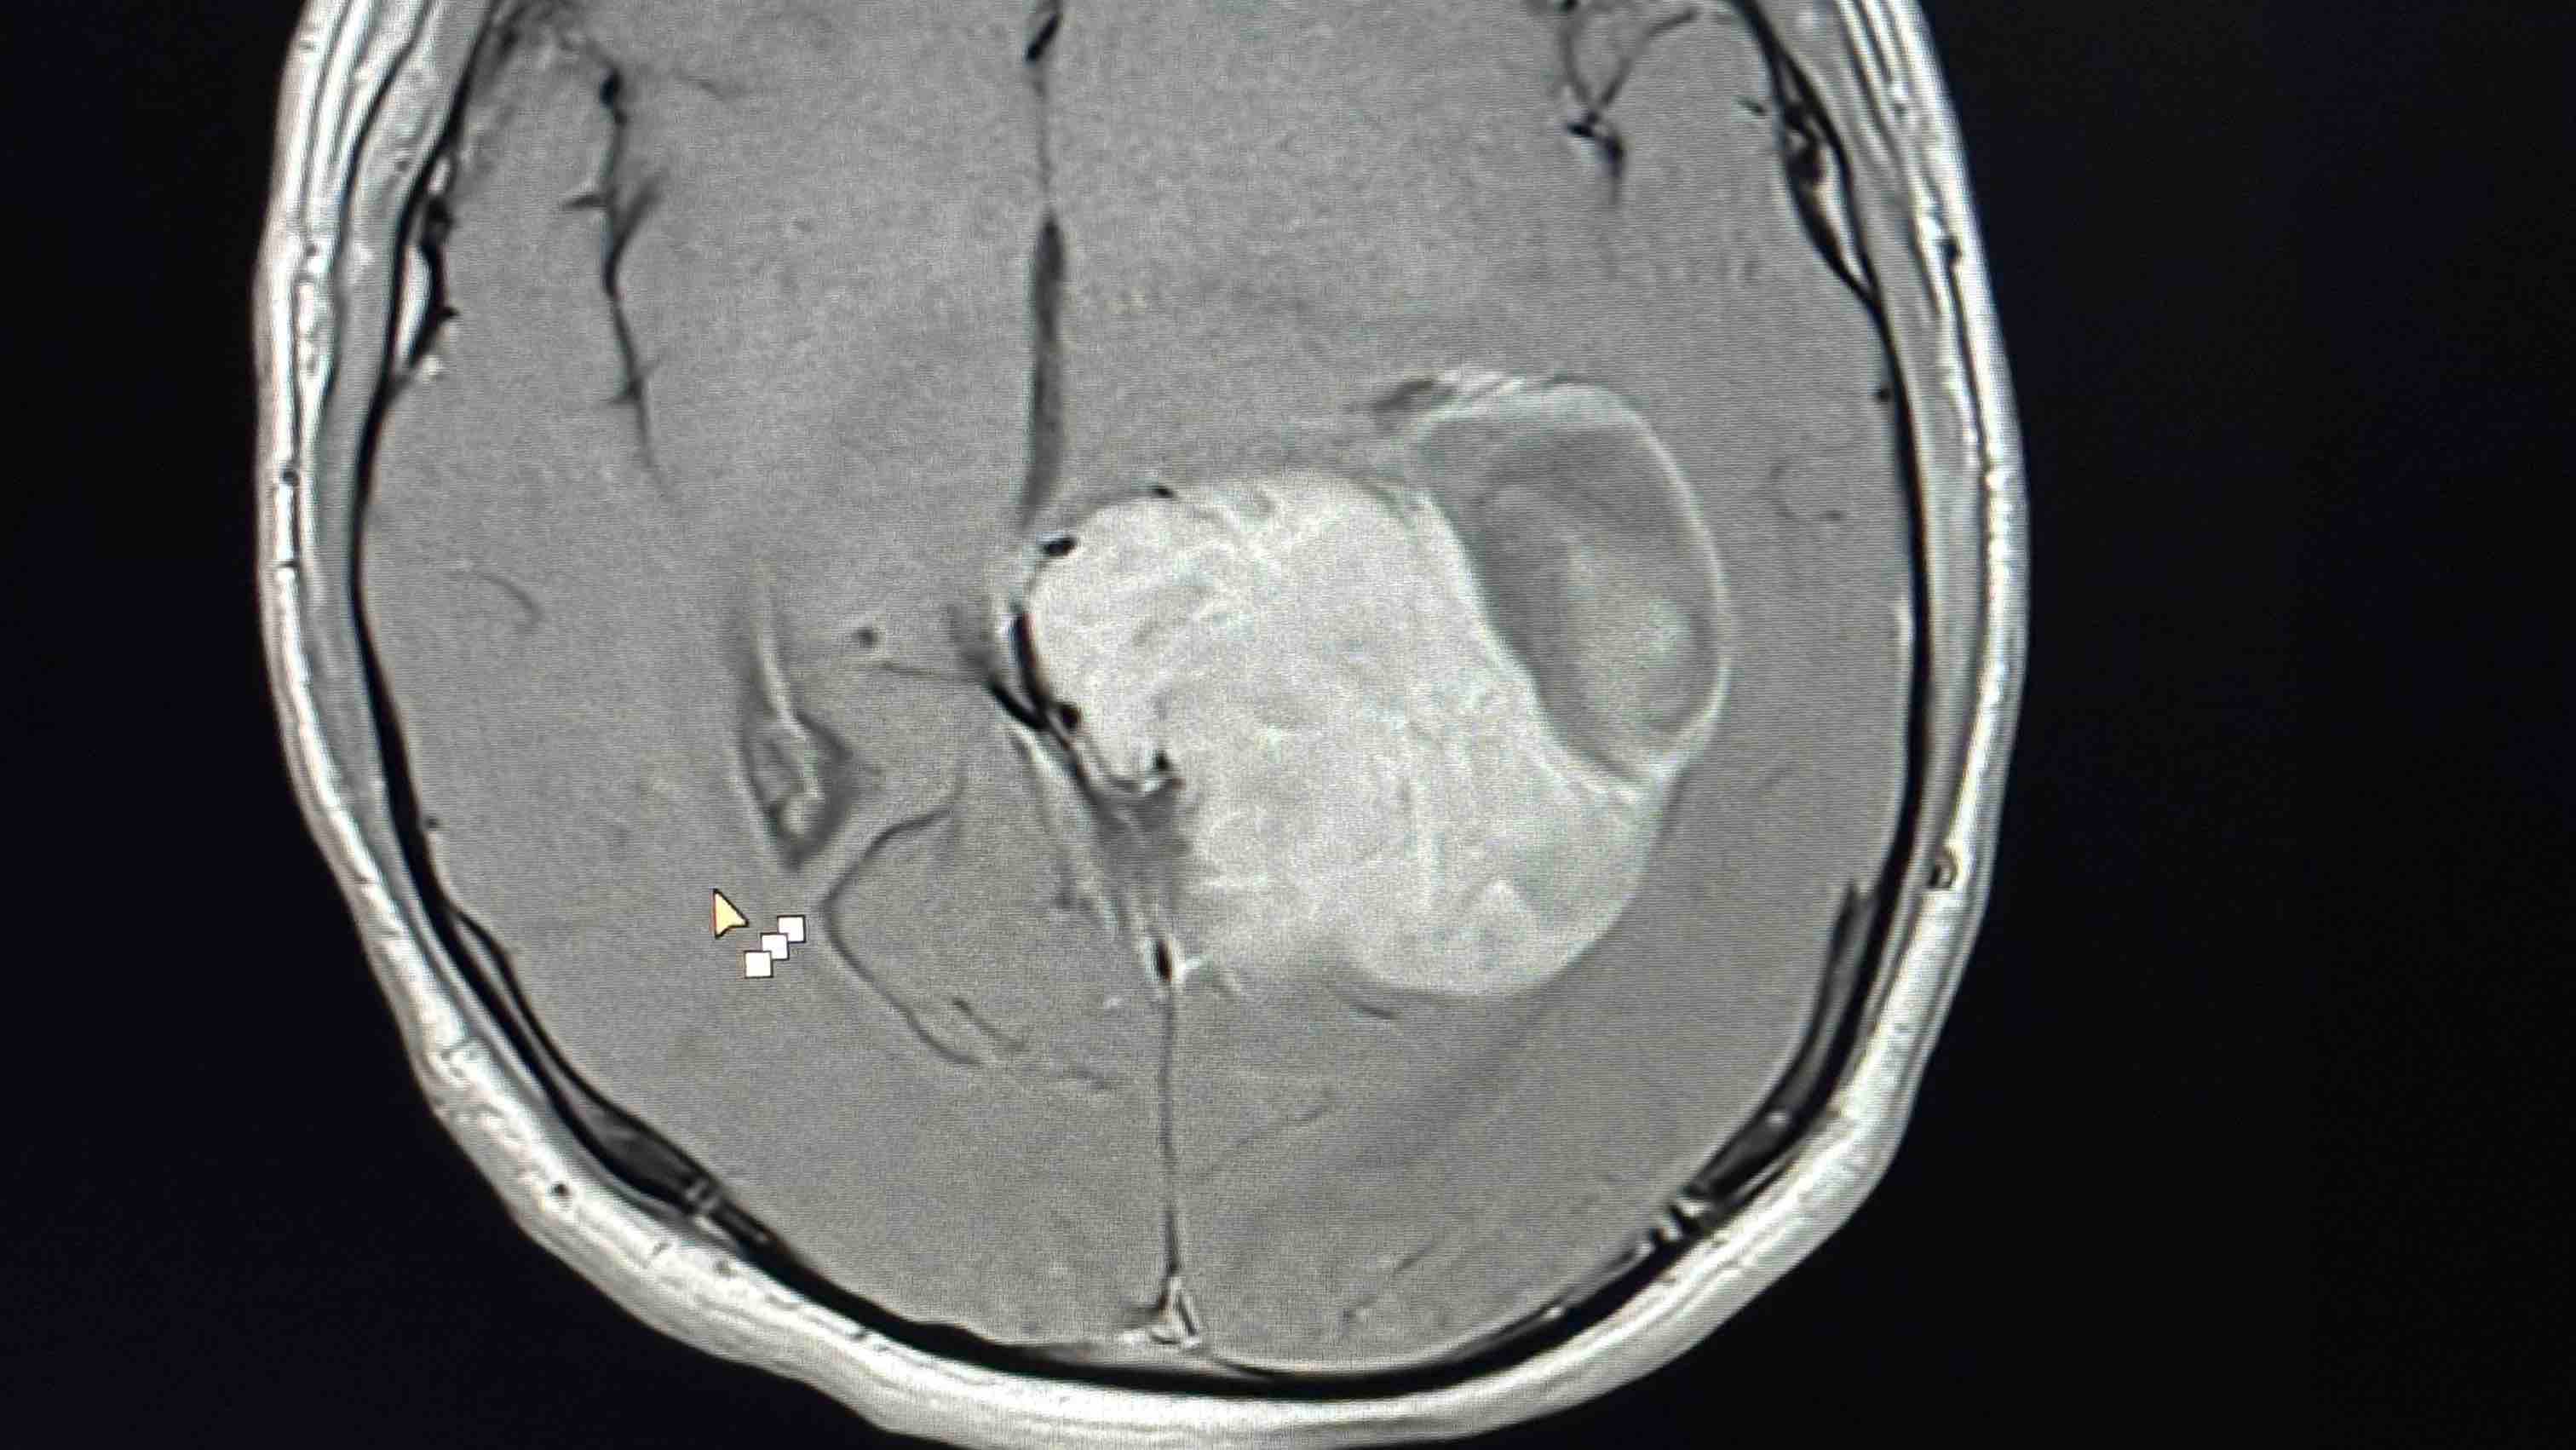

Jared did well today. They were able to get him off the vent. He was eating cheeseburgers and joking around. Unfortunately they only were able to get about 25% of the tumor. They are saying it’s something they’ve never seen before. They said what they didn’t realize during his surgery was as they were “scooping” the tumor it was collapsing in on itself. So they weren’t able to get nearly as much as they thought they did. The mri look just about the same as before the surgery. So now on to plan B. He will remain in the neuroscience ICU. They are giving his brain a few days to heal. Then they want to do an angiogram of the blood vessels in his brain so they can identify the main vessels feeding the tumor. As well as the vessels feeding his brain. Once that is known we still have to wait for pathology report as the first was inconclusive and had to be sent for further testing. Whatever this is, is rare and unknown. Once we get the answers to those two then they will all come together with a plan to go back in and remove, god willing, the remainder of the tumor. This could be in a week. Maybe more maybe a couple days less. He is doing well though. He has issues with his vision and function of his left foot/leg. So for all his friends out there. We are trying to help him as much as we can get through his Snapchat’s and texts. It’s hard for him to read and text back. Please continue the prayers, answers, for complete healing and a prayer for patience for all of us but especially Jared. Who said to me “just tell them to get it out now so I can get back to my life” He is not one to lay around in bed and he was getting anxious about that. So please pray and encourage him to rest and have patience throughout this journey. He is now sound asleep and has had little pain. Thank you everyone!!!! You have no idea how much it means to all of us.

Prayers for J-Rod as we prepare for his second brain surgery tomorrow. We have a couple answers, he has Ependymoma which is a rare CNS tumor that usually occur in younger children. But can occur in teens and young adults as well. We are not sure how long he’s had this but they do feel it’s been pretty slow growing. Imaging has shown that it has not spread. This type can spread through the spine but unlikely to go beyond that. But as far as Jared’s it is localized to the original tumor in his brain. Although massive in size. We thank the good Lord, our Heavenly Father, for that. We don’t have staging yet as that’s an additional and timely part of the pathology and likely won’t have that until next week due to the holiday weekend. Hopes are that he will get the first slot in the AM for surgery. But that’s also dependent on the pediatric neurosurgeon that took over his case. As he has been away on vacation. They want to make absolutely sure he is completely up to date and has a good surgical plan in place. If he needs additional time tomorrow, then so be it and his surgery will be a little later or tomorrow night. PT did get him up using the walker and into the chair. Still lots of struggles with the left side but they were happy with how well he did. It’s a good possibility they will get him in a wheelchair and outside this evening to see the fireworks to local golf course sets off as he can’t see them from his window. That is a process due to his drain. But they are pretty sure we can get that done. Please all continue to keep him in your thoughts and prayers. As always. I thank everyone for the generosity, as of right now there are no medical expenses but we have our expenses to stay here with him, food, accommodations, gas, daily living needs as well as lots of snacks for Jared. Funding also goes to travel back home to take care of things and give his youngest sibling Riley a bit of a break as well as trying to pay bills as I have had a total loss of income right now to be with him and under FMLA. So I thank you all for allowing me to be able to be with my son at all times during this. We pray that after surgery the treatments will be minimal and we are able to get him back home sooner rather than later. There will most likely be at least some radiation therapy depending on if they are able to resect the whole tumor and what the grading/staging is. He will also need physical and occupational therapy, to what extent, we don’t know right now. Again thank you all and I will keep you updated as much as I can after surgery. Let’s get this young man back to the crazy J-Rod that loved to test his mom’s anxiety with his antics.

A little more in depth update from yesterday’s…. Pathology showed a rare tumor called an ependymoma. Only about 200 diagnosed a year. These are usually benign tumors and can be slow or fast growing. They do feel his has been on the slower growing side just based off symptoms. Benign vs cancerous depends on the stage/grade. The highest stage is considered cancerous as it can spread outside the central nervous system and is very aggressive. There is no evidence of that. We are hoping to get that final staging back this week from the lab. Delays due to the holiday weekend. His new surgeon is incredible and has worked with these tumors before. He made us aware of all the mistakes made by the Cedar Crest surgeon. The left side partial paralysis/weakness is due to them going through right side healthy brain to get to the left side tumor and the “bruising, dried blood” on that side has what led to this. He does feel that will resolve with extensive rehab and healing. Last night while helping wash his feet we unintentionally found out he is once again ticklish on that left foot. Which had us all cracking up and gave some relief that feeling is coming back.

So for this tumor. The biggest hurdle is complete resection of it as these tumors do recur and he will be monitored his entire life for them. The hard part is there is a lot of it right by the optic nerve and the nerves that control the RIGHT side of his body. The surgeon does feel that with removal he will experience some of this but is hopeful with in patient rehab his brain and the nerves will bring most or all function back. That’s not something we can predict. Surgery is scheduled for first thing Monday (tomorrow) morning. After surgery, once he is stable they will run another mri to make sure they got it all, as sometimes the margins may get a little “fuzzy” but typically the margins are fairly clear. IF they see anything on the post op MRI they will return to the OR on Tuesday to remove any remaining cells. IF they can safely do so without further complications. If not. Radiation may be needed but radiation is not always helpful with this type of tumor and there is no clinical evidence that supports chemotherapy is helpful. So let’s all prayer for a safe and complete resection!!!

For those that may not follow my facebook posts, I apologize for delayed updates. Jared had his second brain surgery yesterday. Everything went extremely well with no complications. He had a rough night last night from post op pain. This was the first time since that first night we got this diagnosis that he has been in pain and for that we are thankful. For today Jared had less pain today which was great. Still a little more pain this evening but is resting comfortably now after another pain reliever/muscle relaxer cocktail. He got his post op MRI and no visible signs of any remaining tumor!!! Praise God!! We still have a long wait for complete pathology to determine if they will do radiation for any microscopic cells that may linger that imaging can’t pick up. He did get up and in the chair for a bit today. Still struggling with that left foot, so he finally got the brace to help with that when walking. They had originally planned on blocking his “brain drain” or “charging part” (as he calls it) tomorrow for 24 hours and then a CT on Thursday to see how he is doing. But he’s had a slight fever of 100.9 and elevated white blood cell count. So I am not sure at this time if that’s still the plan. They aren’t too concerned but they are being proactive and started him on 2 IV antibiotics while we wait for cultures of the CSF, blood, urine, and nasal swab to come back. Will talk more in the AM to his surgeon to see if that’s still safe to do. If all is safe and clear he may possibly be able to get out of PICU Thursday or Friday and moved upstairs. Please continue to prayer for Jared that this fever is a simple post op fever and not an infection. As well as continued prayers for best possible outcome with pathology and that he will start to regain sensation in the left foot. He still has a long road ahead of him but he is a fighter. Pictures are pre op and post op MRI images.